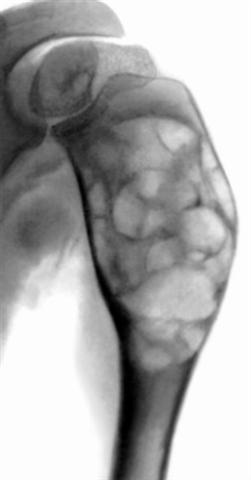

Рис. 2б). Динамика развития солитарной кисты кости: солитарная киста в фазе отграничения у того же больного через 2 года, полость уменьшилась, стенки ее уплотнились, между кистой и зоной роста нормальная кость.